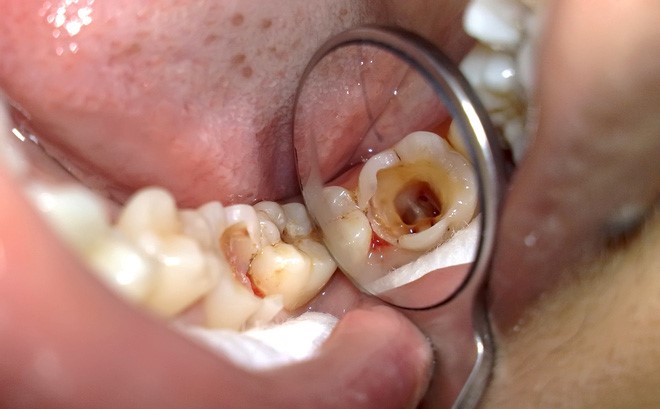

Vi khuẩn gây sâu răng không chỉ tấn công ở men răng mà chúng còn thâm nhập vào lớp ngà răng, tủy răng gây đau nhức dữ dội. Nếu không tiến hành khắc phục sớm bệnh có thể gây ra các biến chứng như viêm tủy răng, nhiễm trùng, răng gãy còn chân, răng lung lay thậm chí là mất răng sớm.

(Viêm tủy răng gây đau nhức dữ dội, ảnh hưởng nghiêm trọng đến lối sống của người bệnh)(**)